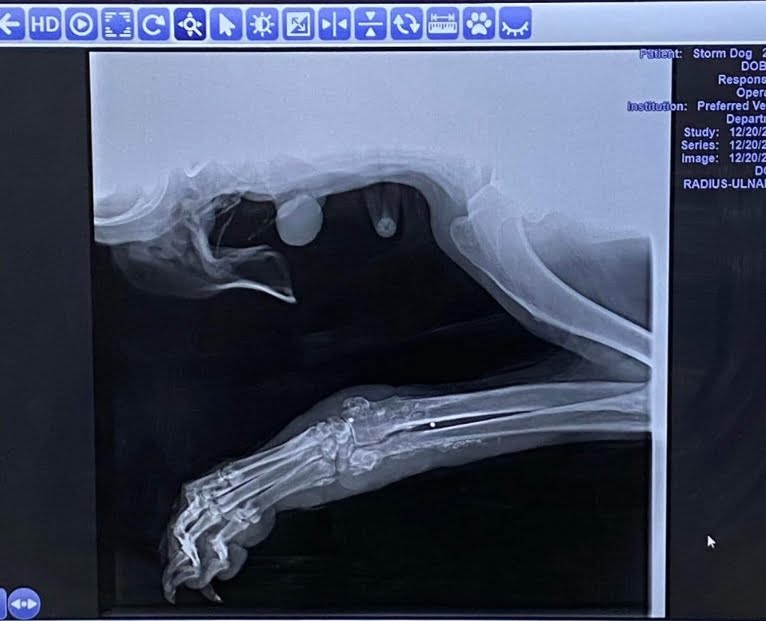

MCAS took Jake to a local veterinary clinic to assess his injuries. The storm had left him bruised but he also had an unusual leg injury. X-rays revealed that Jake had been shot in the leg. It was full of buckshot that was causing a life-threatening infection. To make matters worse, the buckshot had begun to calcify in Jake’s joints, making it unsafe for the veterinarians to remove it.